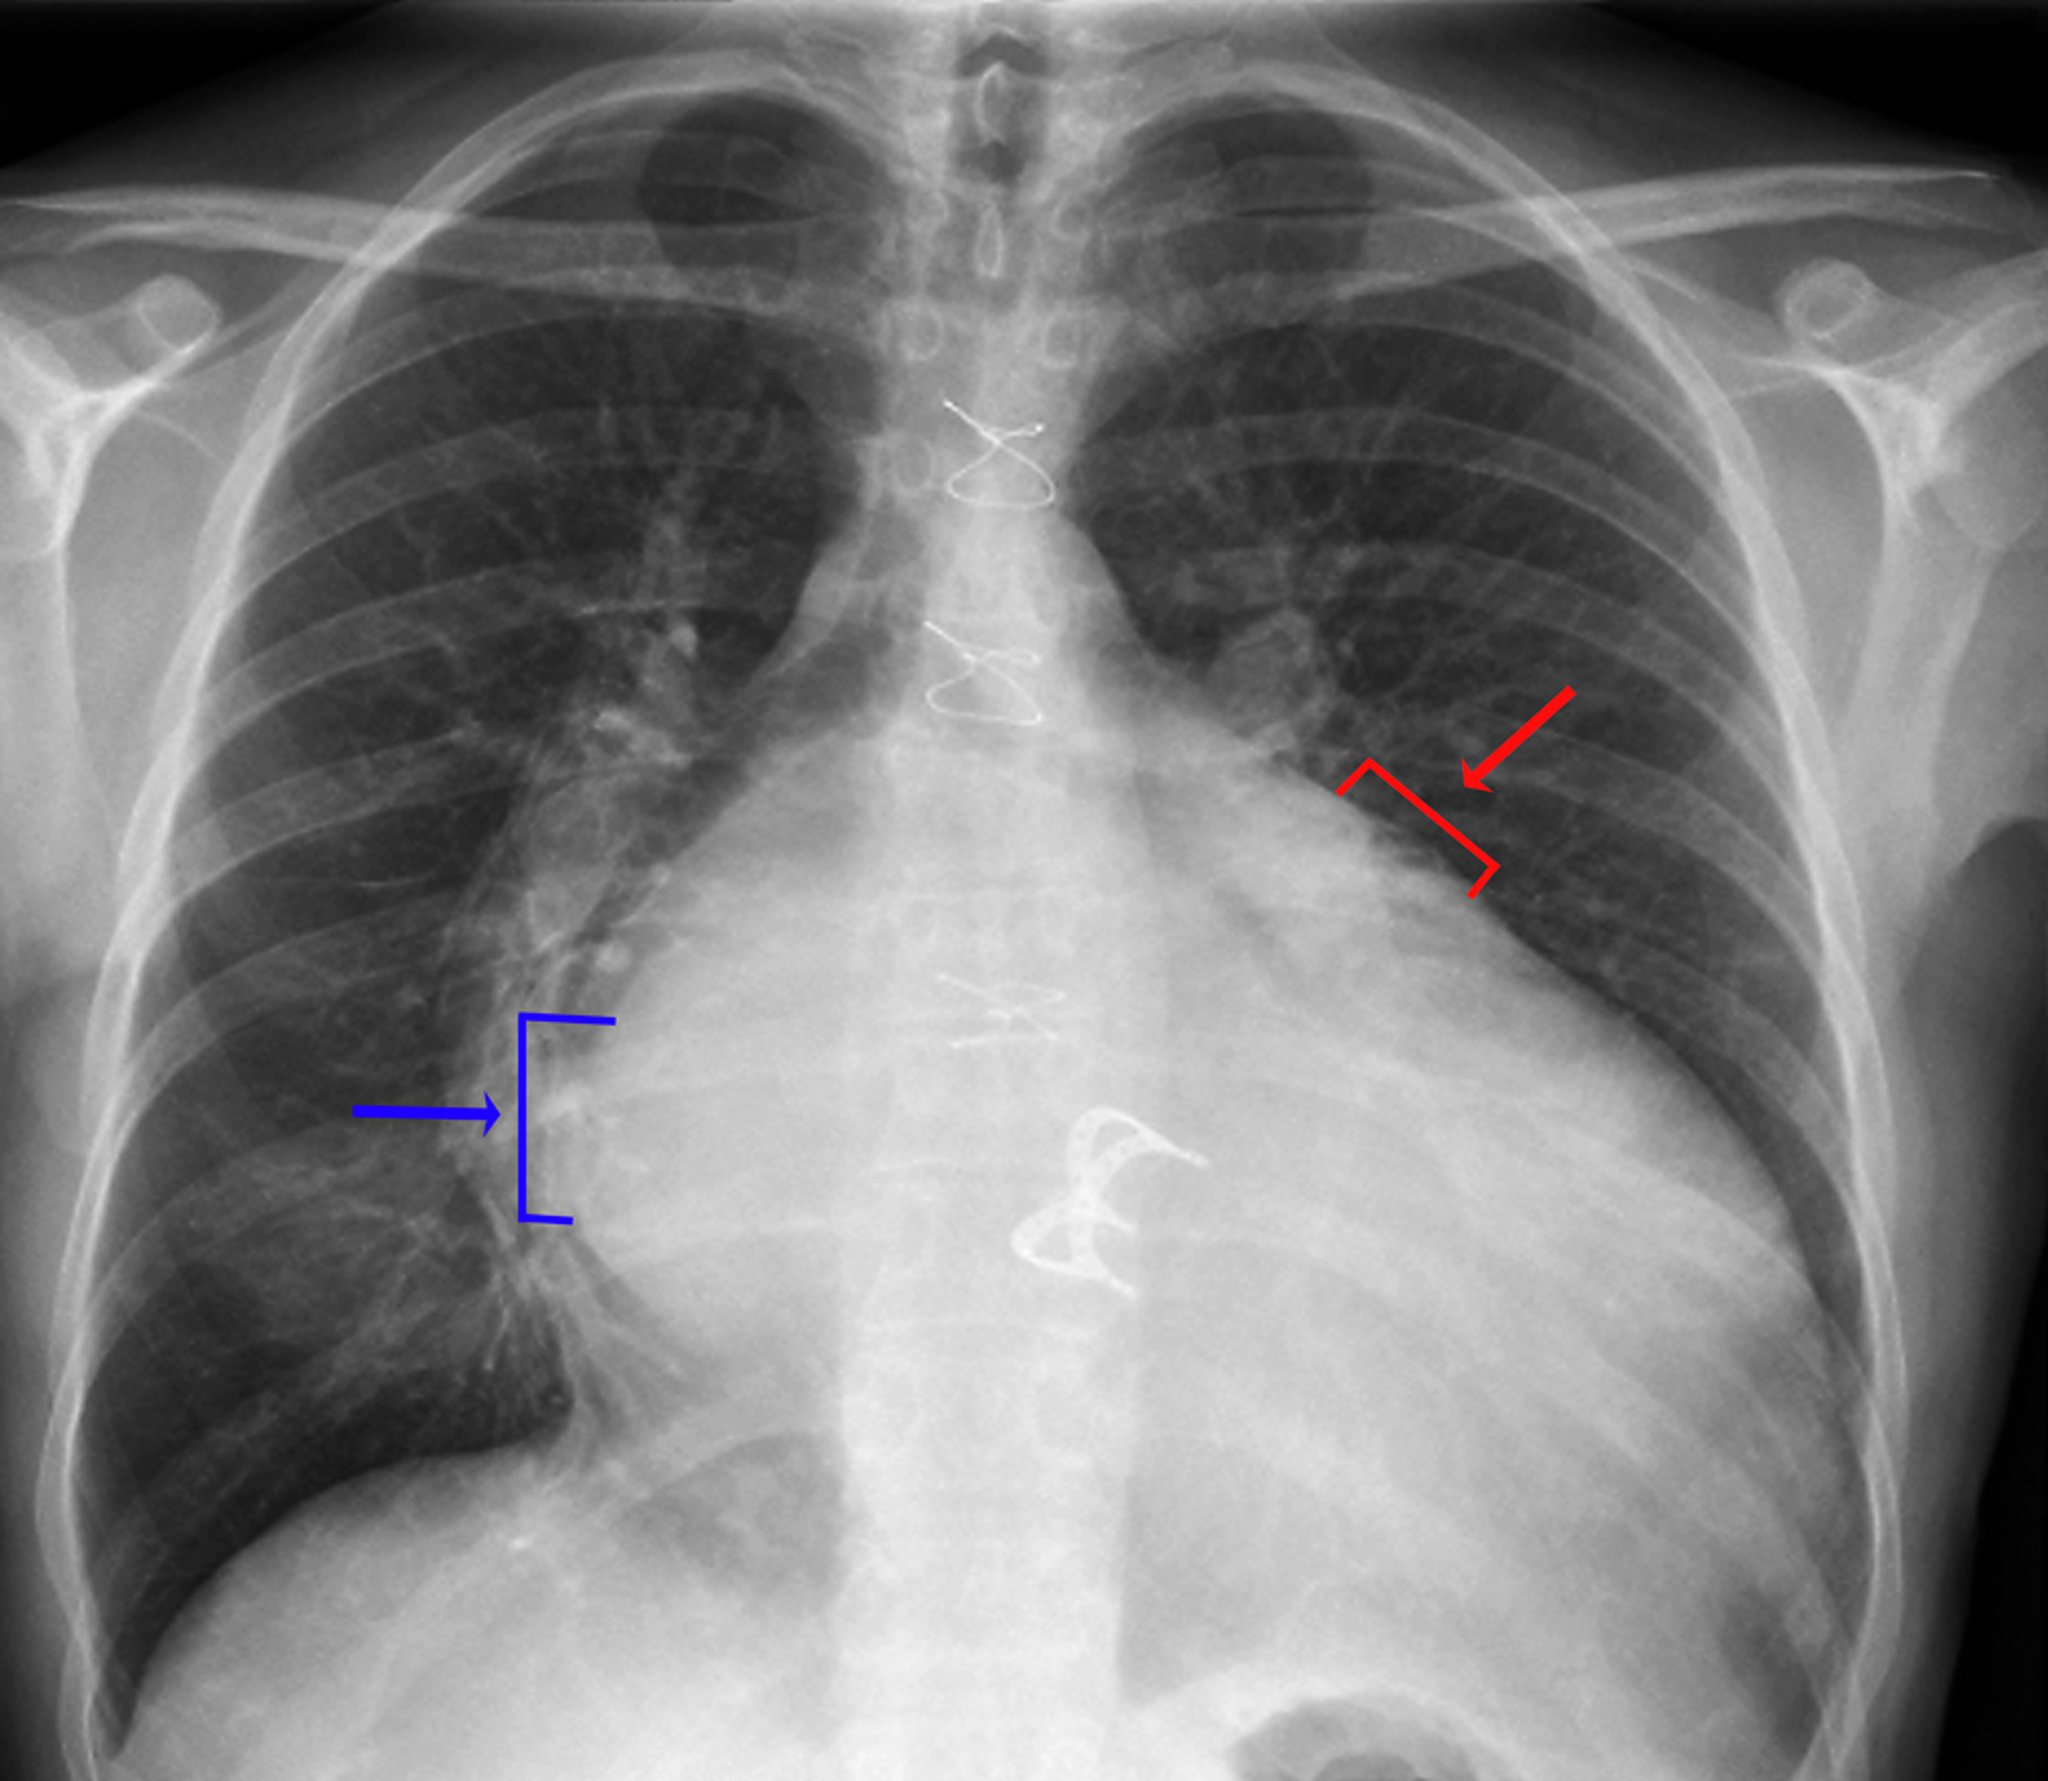

Rx thorax (valvule cardiaque prothétique)

Les signes d'hypertrophie de l'oreillette gauche comprennent la densité visible de l'oreillette gauche dans l'hémithorax droit (flèche bleue, signe de double densité), une augmentation (> 7 cm) de la distance entre le bord de l'oreillette gauche dans l'hémithorax droit et la bronche principale, une convexité le long de la bordure supérieure gauche du cœur provoquée par l'augmentation de volume de l'auricule gauche (flèche rouge) et l'élargissement de la carène avec augmentation de la séparation entre les bronches principales gauche et droite. Les signes d'augmentation du volume du ventricule gauche comprennent un agrandissement évident de la silhouette cardiaque et un déplacement vers la gauche et le bas du bord gauche du cœur.

ZEPHYR/SCIENCE PHOTO LIBRARY